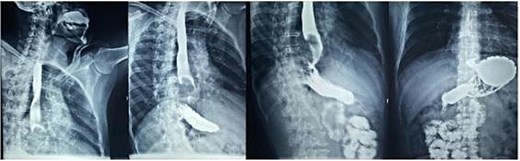

A 48-year-old male presented with a two-year history of progressive dysphagia accompanied by chest pain, without prior radiation exposure, NF1, or other malignancy risk factors. Esophagogastroduodenal contrast series (Fig. 1) revealed a radiolucent, intraluminal mass in the distal esophagus causing partial obstruction. Consequently, an upper endoscopy (Fig. 2) was performed, which confirmed an obstructive tumor in the lower third of the esophagus, with associated duodenitis and erosive gastritis.

Esophagogastroduodenal series: Radiolucent image in the distal third of the esophagus forming a convex mass due to partial obstruction of the passage of contrast into the stomach.